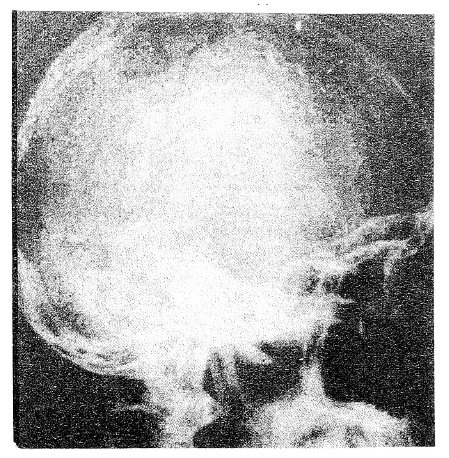

При гипертензионно-гидроцефальном синдроме (рис. 2) отмечены остеопоротические изменения верхушки спинки седла — уменьшается плотность спонгиозного вещества, убыль которого на 20% определяется рентгенологическим методом исследования. Позднее порозным становится кортикальный слой, что проявляется уменьшением его плотности и четкости.

Рис. 2. Рентгенограмма черепа в правой боковой проекции больного С., 25 лет, страдающего гипертензионно- гидроцефальным синдромом, обусловленным краниофарингиомой. Отмечается усиление рисунка пальцевидных вдавлений. Истончение диплоэ. Вторичные изменения турецкого седла в виде порозности верхних его деталей с расширением переднезаднего размера

Вслед за изменениями спинки турецкого седла остеопорозу подвергается его дно, причем передний скат в этом случае изменяется редко. Деструктивные изменения турецкого седла связаны с опухолевыми процессами, исходящими из основной кости; инволютивные изменения турецкого седла выражаются остеопорозом его деталей.